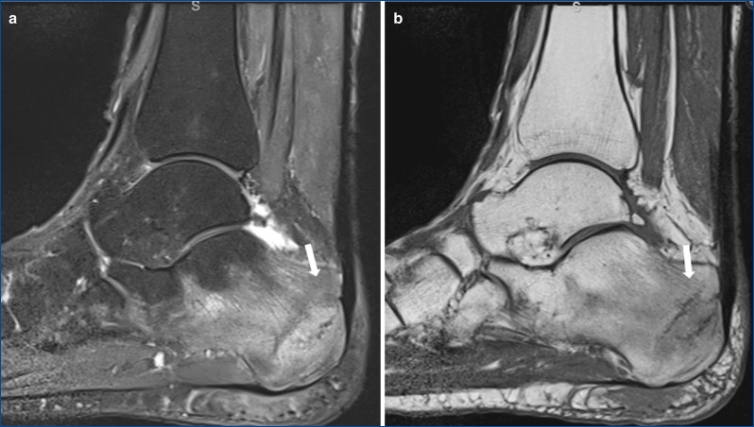

피로 골절 식별 방법

피로 골절은 초기 단계에서는 X-레이 검사에서 잘 나타나지 않을 수 있습니다. 따라서 의료 전문가는 환자의 증상과 활동 수준, 그리고 발뒤꿈치를 직접 살펴보는 신체검사를 바탕으로 진단을 내립니다. 스트레스 골절이 의심되는 경우 MRI 또는 골 스캔과 같은 보다 정밀한 영상 진단 방법이 사용될 수 있습니다.